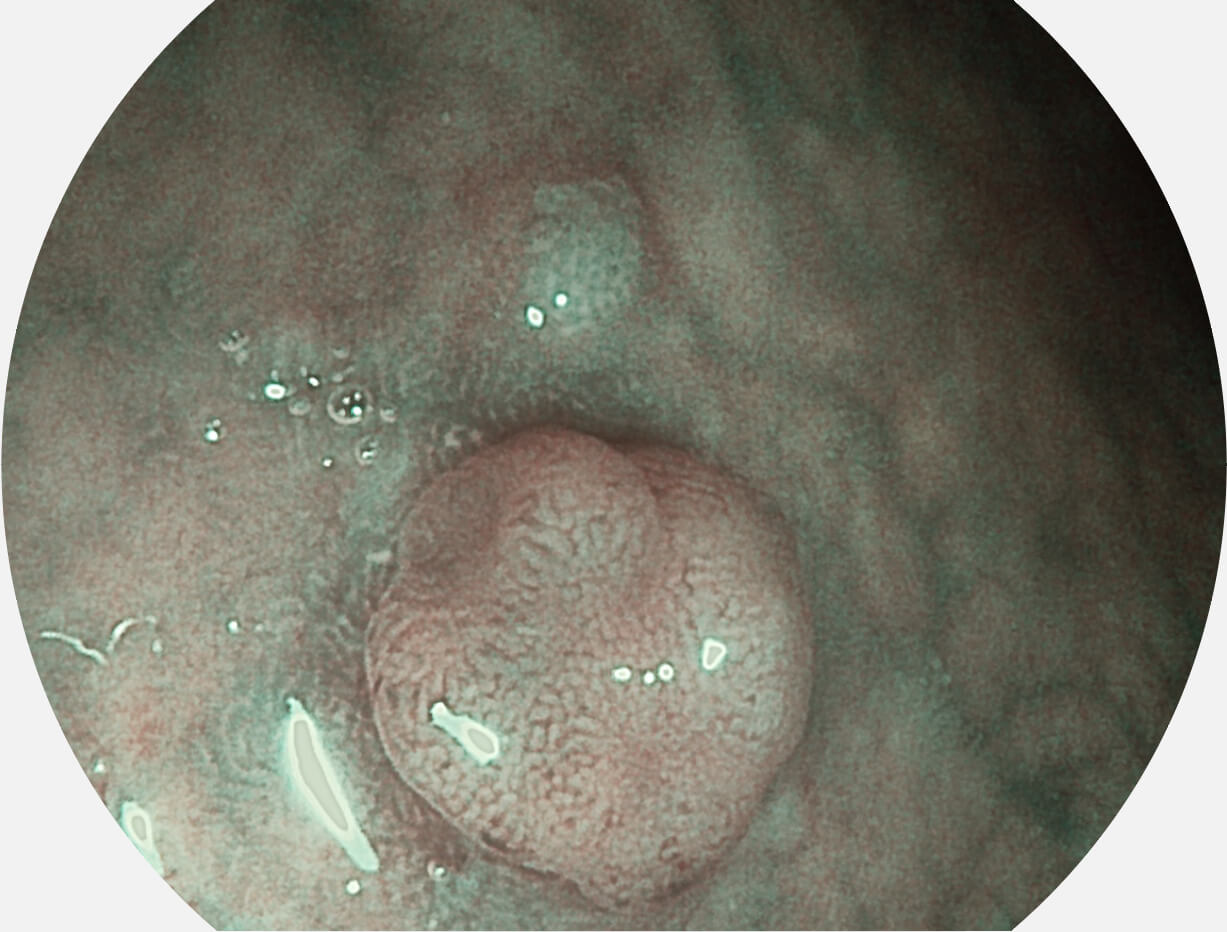

图像具有高亮度、高黏膜血管颜色对比度的特点,且不改变粘液、食物残渣、粪便的基本颜色,可在中远景下进行观察,助力消化道早期疾病的诊断。

• 白光图像 SFI图像